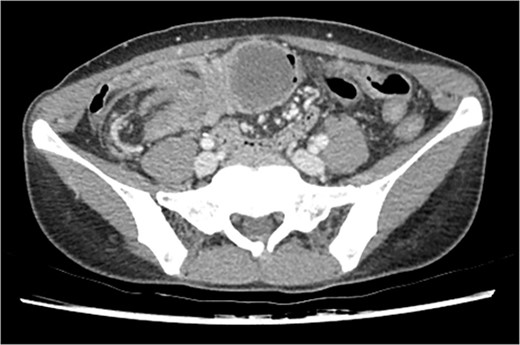

Initial vitals were normotensive and stable, without fever. Physical examination indicated mild lower abdomen tenderness, but the abdomen was rather soft and not distended or tympanic. Laboratory tests were all within normal limits except for the white blood cell differential count, showing an elevated segmented neutrophil ratio of 89.4%. Formal CT readings highlighted a 6.2 cm sized septated cystic tumor of the right colon as the leading point of the colonic intussusception (Fig. 1). Radiologists suggested a differential diagnosis of duplication cyst, mucocele, endometriosis, lymphangioma, or myxoma.

Initial CT scan of the colo-colic intussusception and the septated cystic tumor.